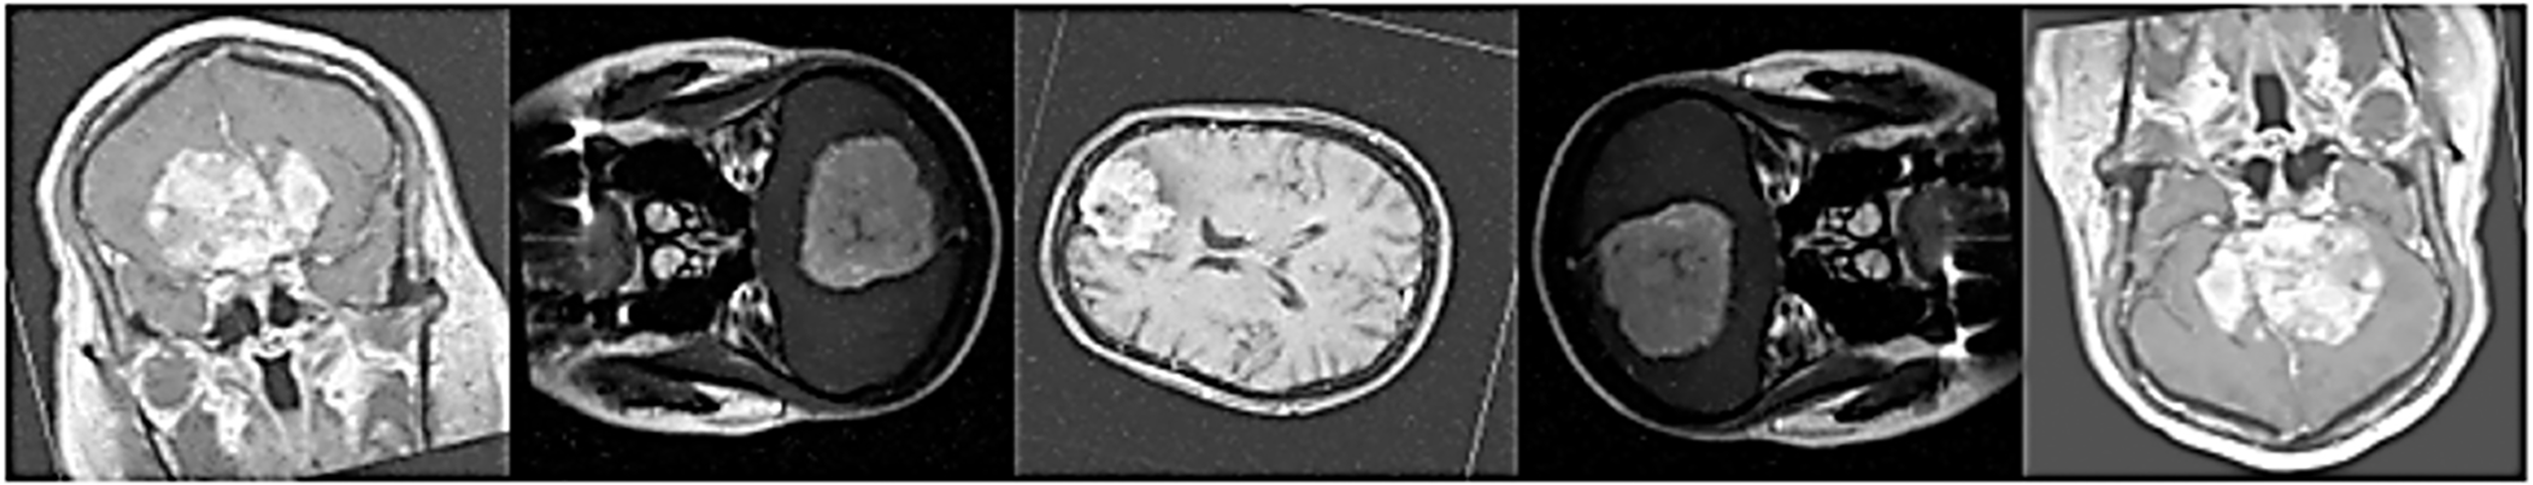

The suggested Fine-Tuned EfficientNet-B6 model performs marginally better on the public brain tumour dataset than on the custom dataset, according to a comparison of the findings in Tables 5 and 6. The model consistently scores between 99.10% and 99.11% in accuracy, precision, recall, F1-score, and specificity across all four classes (Meningioma, Pituitary, Glioma, and No Tumour), as shown in Table 5. On the other hand, Table 6 shows that, although still good, the model’s performance on the custom data set falls between 97.8% and 97.9% for most assessment measures. The results show that the model retains strong generalization and dependable classification power across both datasets, despite this slight decline, proving its efficacy in multiclass brain tumor identification.